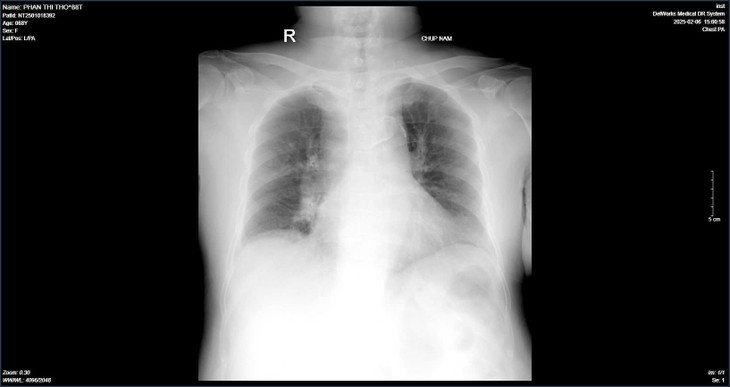

| Hình ảnh chụp phổi của bệnh nhân T. khi vào viện và hình chụp phổi sau quá trình điều trị - Ảnh BVCC |

Theo ghi nhận từ khoa Bệnh nhiệt đới – Bệnh viện Nội tiết Trung ương đang điều trị cho bệnh nhân Phan Thị T. (88 tuổi) mắc virus cúm A. Cách vào viện 2 ngày, bệnh nhân xuất hiện ho khan, sốt 38-39 độ C, đi mua kháng sinh, long đờm uống không đỡ. Cách vào viện 1 ngày bệnh nhân sốt cao, ý thức chậm nên được người nhà đưa vào bệnh viện Nội tiết Trung ương.

Sau khi tiếp nhận thăm thăm khám, bệnh nhân được chẩn đoán: Suy hô hấp, viêm phổi, cúm A- Đợt cấp suy thận mạn; Đái tháo đường typ 2, tăng huyết áp, rối loạn lipid máu, suy tim, bệnh thận mạn giai đoạn 3, biến chứng thần kinh ngoại vi. Bệnh nhân có tiền sử cắt cụt 1/3 cẳng chân trái do bệnh động mạch ngoại biên.

Sau nhập viện, bệnh nhân được điều trị tích cực bằng thuốc kháng virus, kháng sinh, oxy liệu pháp, kiểm soát dịch ra vào, đái tháo đường, tăng huyết áp; Chữa triệu chứng, nâng cao thể trạng, tập phục hồi chức năng. Sau 4 ngày điều trị, bệnh nhân tỉnh, tiếp xúc tốt, cai được oxy, ăn uống bình thường, chức năng tim, chức năng thận cải thiện.